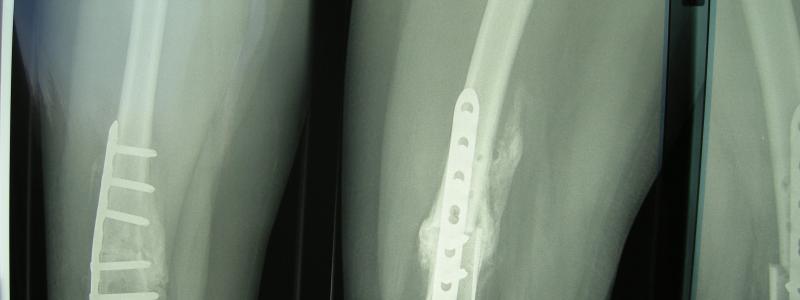

XRays